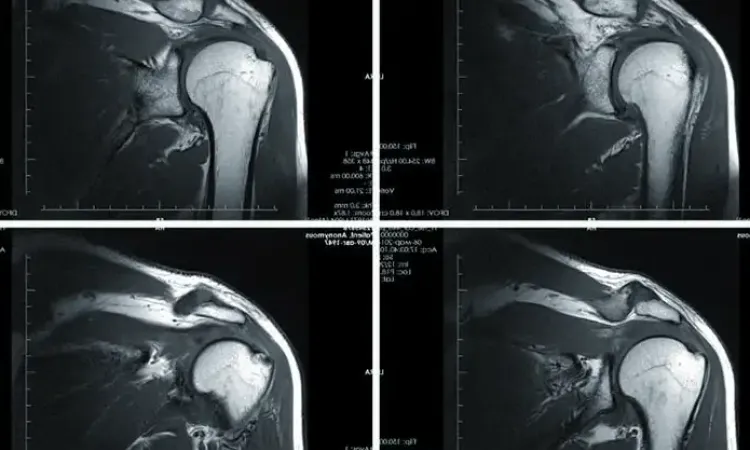

Причины развития патологий разнообразны — от воспалительных изменений до аутоиммунных болезней. Требуется целый комплекс диагностических мероприятий для постановки диагноза. Одним из наиболее информативных методов является магнитно-резонансная томография. МРТ позволяет визуализировать детальное анатомическое строение, что значительно ускоряет диагностический поиск.

В основе работы томографа лежит воздействие магнитного поля на тело человека. Под его действием возникают колебания атомов водорода, которые распознаются специальными датчиками. В последующем при помощи компьютерных технологий колебания превращаются в изображение, которое врач видит на экране.

МРТ — один из наиболее безопасных методов диагностики. Магнитное поле не оказывает никакого воздействия на здоровье человека, в отличие от рентгеновских лучей. Исследование может выполняться неограниченное количество раз, не требует специализированной подготовки. Такой способ диагностики применяется практически у всех категорий больных в любом возрасте.

Магнитно-резонансная томография — золотой стандарт при диагностике патологии со стороны опорно-двигательного аппарата. В центре «МРТ на Каширском шоссе» применяется современное оборудование экспертного класса, которое позволяет проводить детальнейшее исследование. Это значительно ускоряет постановку диагноза, приближает время начала терапии и улучшает дальнейший прогноз. Наши специалисты применяют индивидуальный подход к каждому пациенту и прилагают все усилия для обеспечения физического и психологического комфорта.